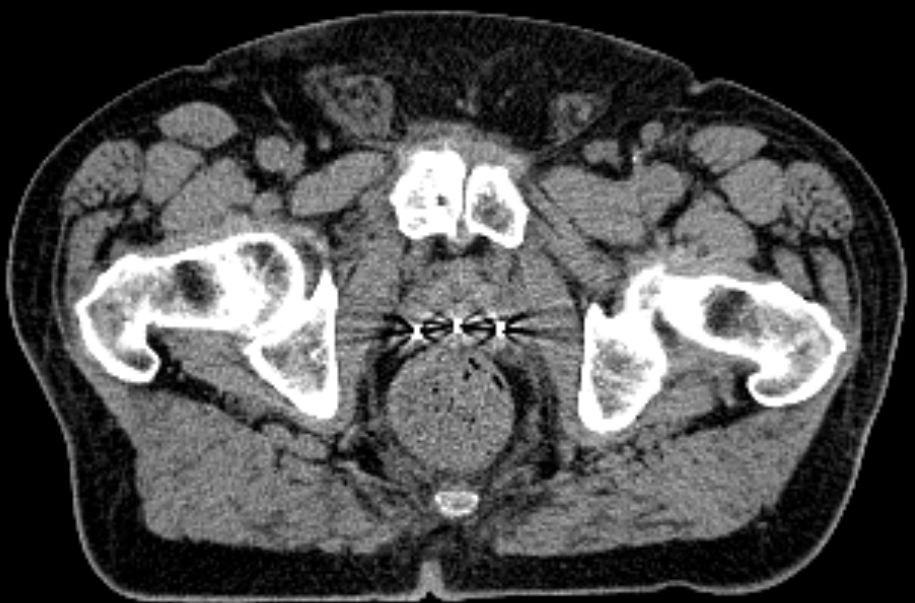

3 Marker wurden in der Prostata plaziert.

Beam View

Selbst im MV-Beamview sind die 3 Marker erkennbar.